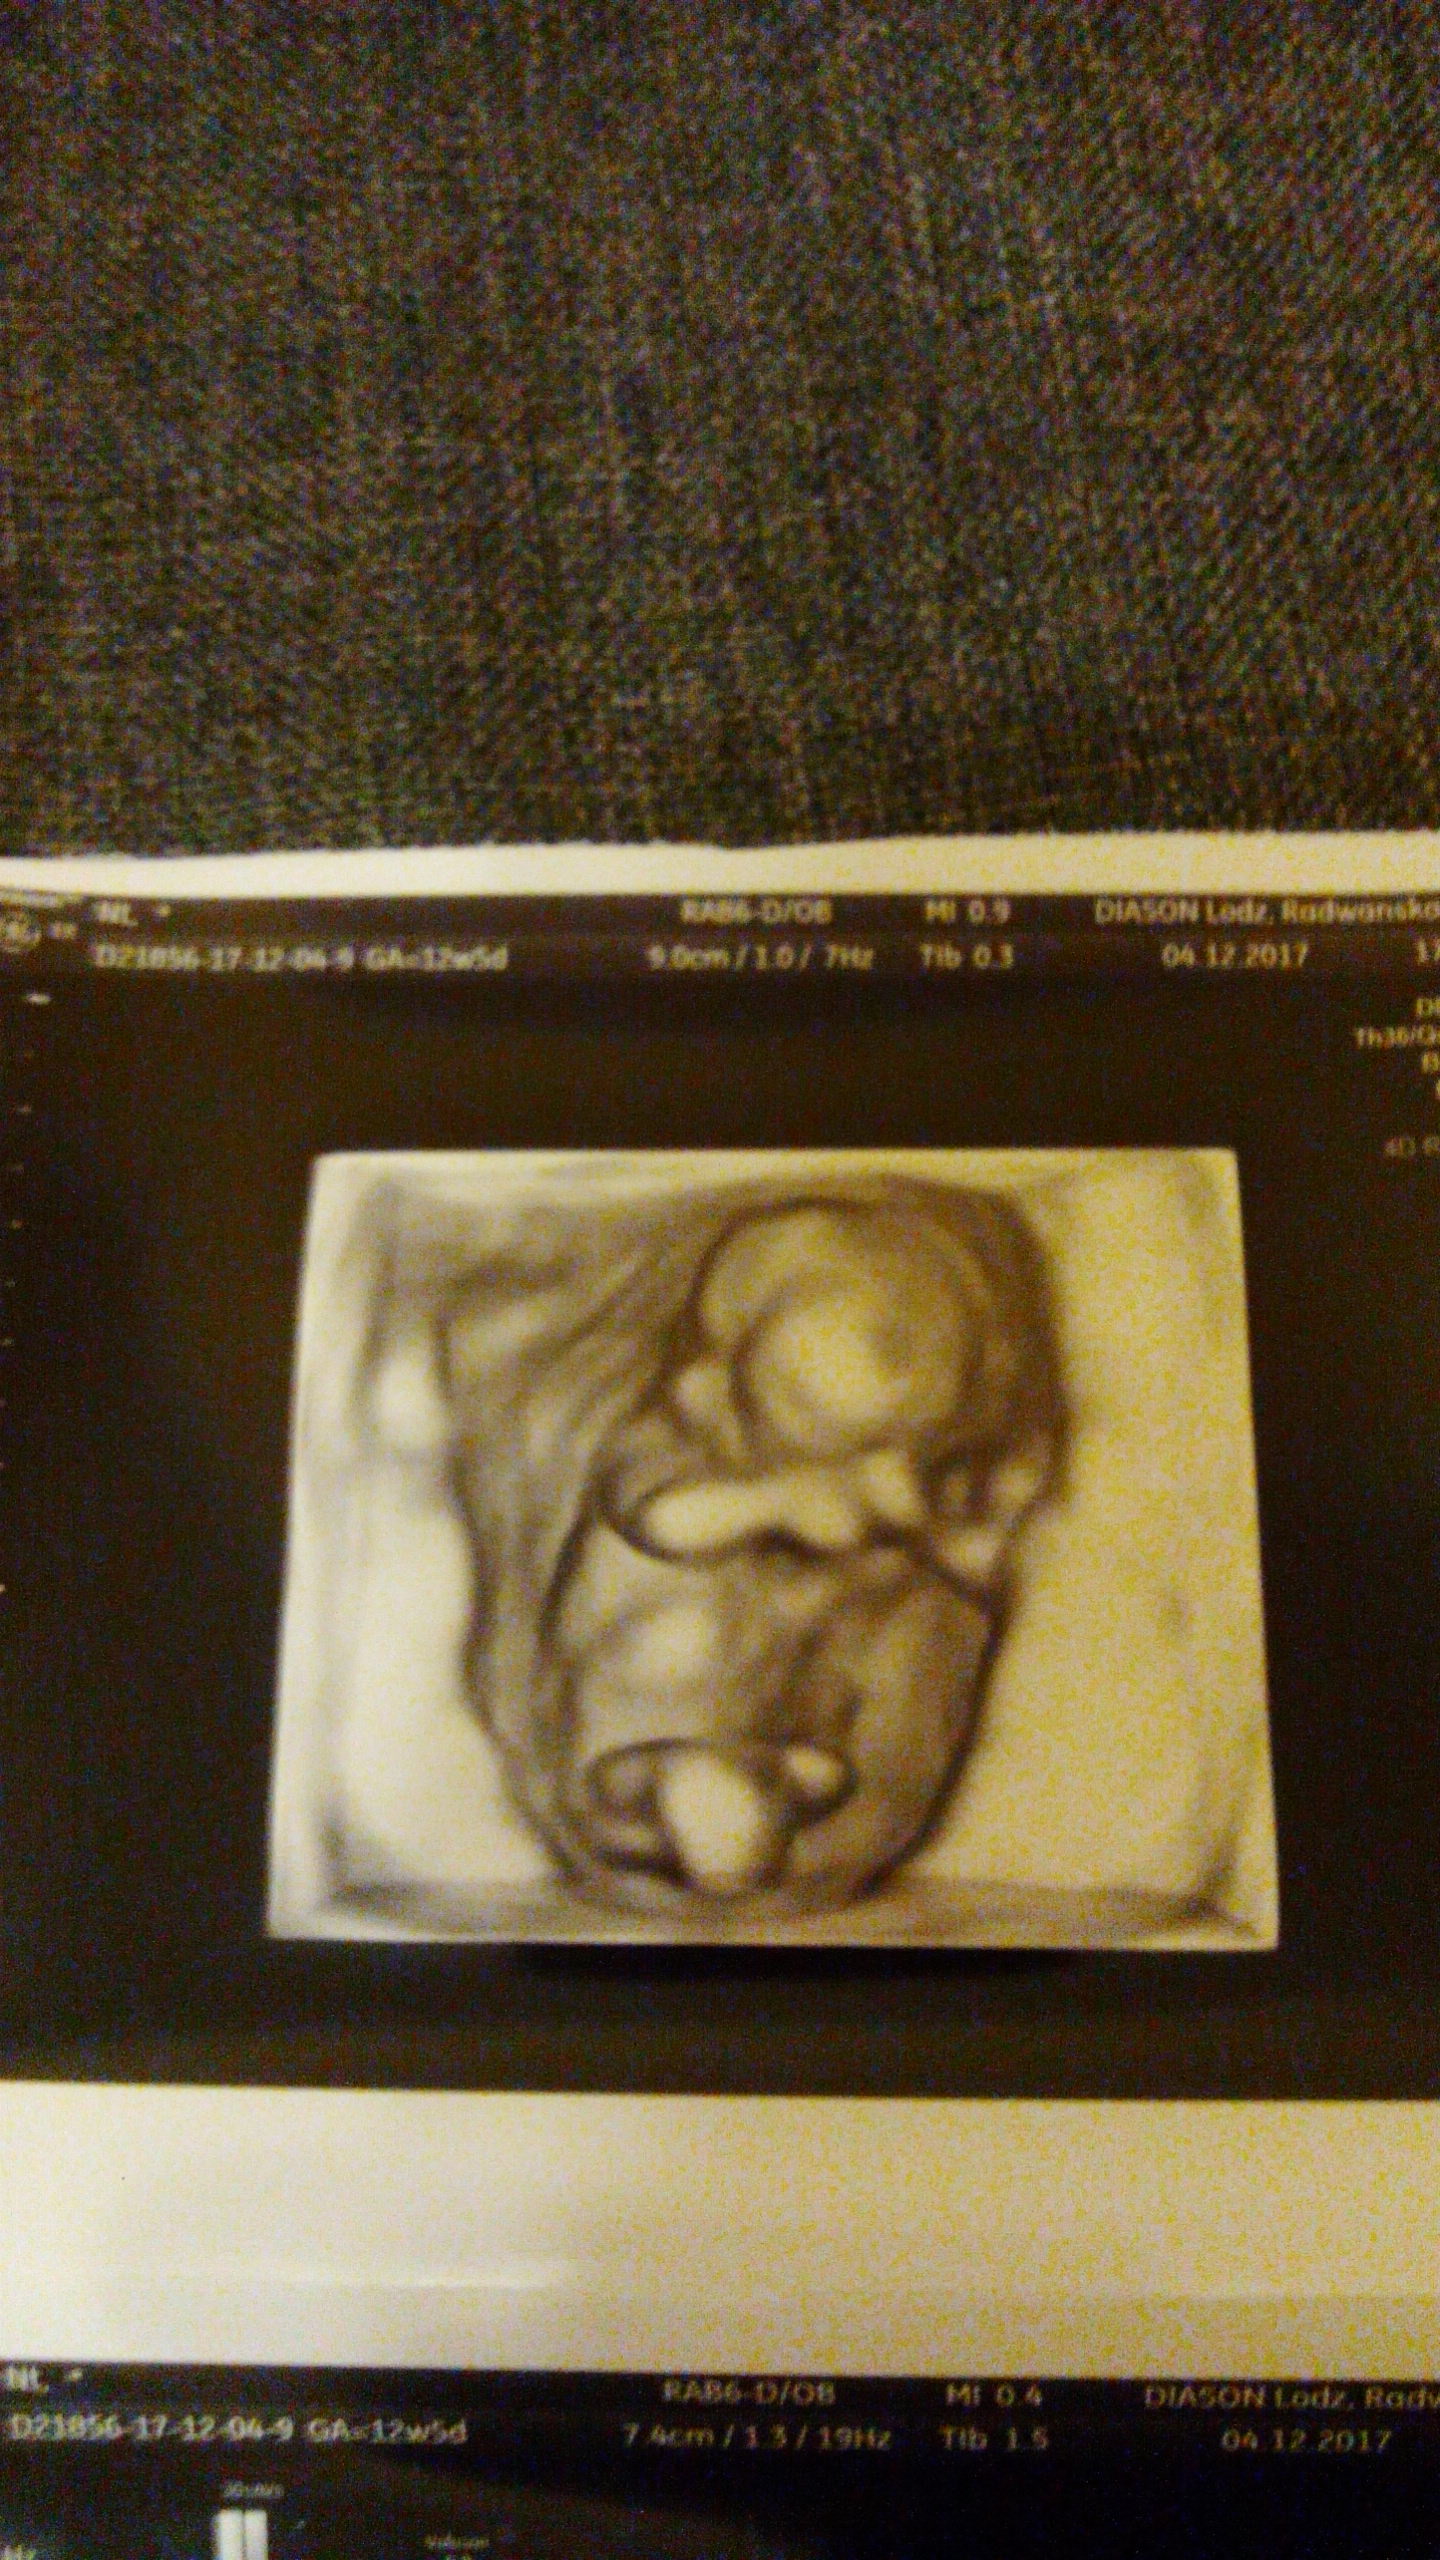

A co do maleństwa to ma już od głowy do pupy 96mm, serduszko bije ładnie - jedno co to w takiej dziwnej pozycji leżał

Łożysko mam na tylnej ścianie [na szczęście sama umiem robić USG i widzę bez opisywania prze ginekologa co i jak, bo tak to bym NIC nie wiedziała, bo ani słowa przy może minutowym badaniu nie powiedziała] i on jakby na plecach na nim leży - taka chyba średnio wygodna pozycja